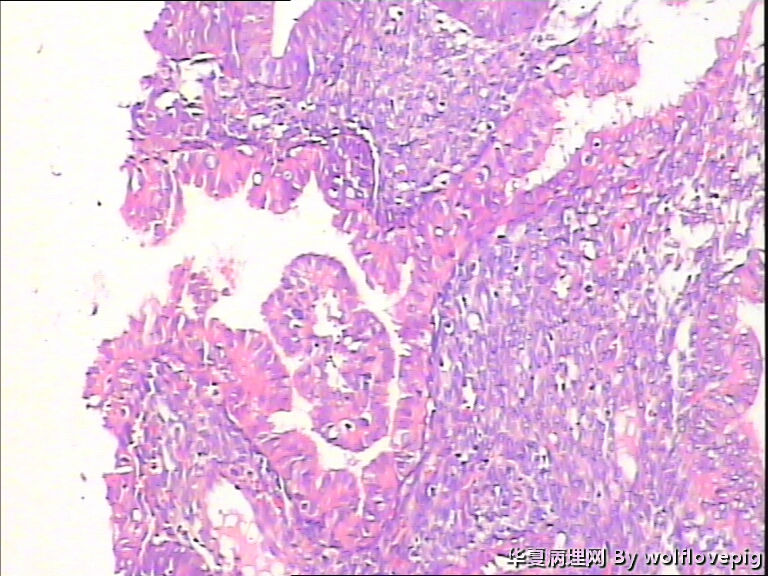

求助,子宫内膜!

48y

• 求助,子宫内膜!图2

图2